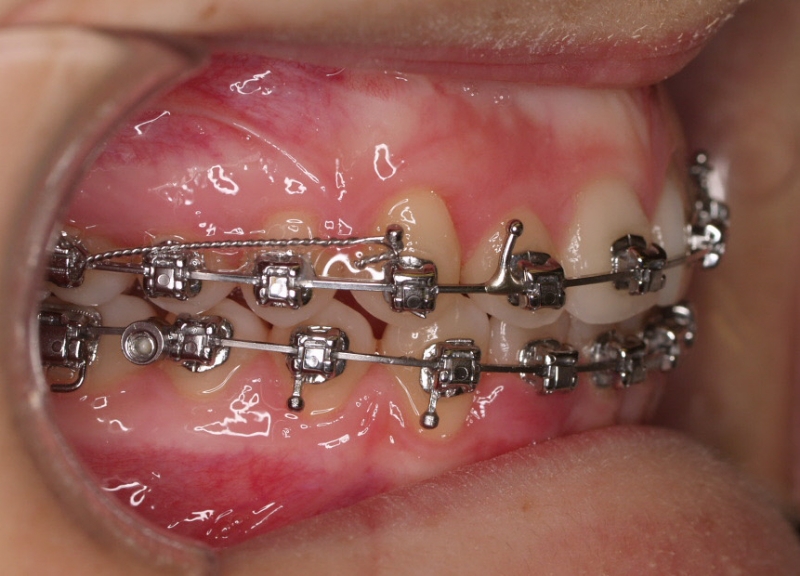

Clase II paciente 15 años

Con lo que decide realizarse un tratamiento de ortodoncia de duración de 24 meses con brackets damon Q.

CASO COMPLETO: